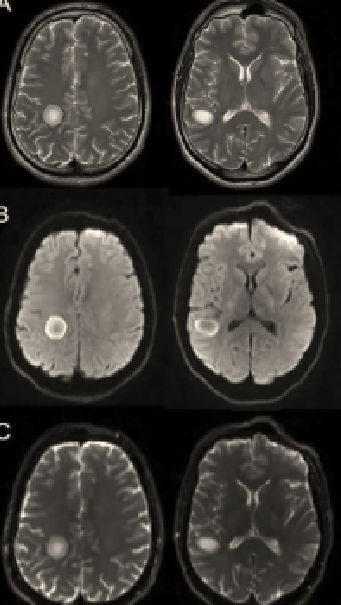

头颅MRI:可见右侧颞枕交界皮质下白质、额顶交界区半卵圆中心两处病灶,呈圆形卵圆形,T2高信号,环形弥散受限,对应区域ADC反转不明显。

诊断: 同心圆硬化(Baló’s concentric sclerosis)

MRI表现:Baló’s 在T1像的特点是多个等、低信号交替的同心圆,在T2加权序列上表现为围绕高信号圆心(风暴眼)的高低信号环,也有其他模式如玫瑰、康乃馨甚至马赛克形状的报道。

病灶有轻微水肿。DWI序列可见弥散受限,多位于病灶边缘。增强序列可见强化,多位于病灶外周边缘,也可见到与T2高信号匹配的多层环形强化。

关于这个问题目前尚没有一个确切的标准,有学者呈高低信号交替1次以上即可考虑Balo,但有学者称信号改变≥2次可考虑“Balo-like”,实际上和交替1次含义差不多,总之不是均匀一致的高或者低信号即可。文献中给出的交替1次的影像如下:

再典型一点的如下(红色箭头即风暴眼(storm center)):

序列更全一点的:

图自:Rev Neurosci. 2018 Nov 27;29(8):873-882.

上述文献病例均较为典型,病灶有着明显的分层。但早读病例中分层并不明显,那么能诊断同心圆硬化吗?这就牵扯到第二个问题:同心圆是从中间向四周涟漪样播散还是多个环形一起出现?

更多观点认为同心圆硬化是从中心向四周离心播散产生的,中心位置可能是由于炎症因素导致小静脉血管通透性增加,播散时,边缘的缺血预处理(ischaemic preconditioning)使得髓鞘相对保留,如此反复形成了特征性的同心圆。所以不难理解,Balo是动态发展的,其早期可以表现为均匀信号改变,类似ADEM、脑脓肿或者肿瘤,后期也可以发展为典型的脱髓鞘软化灶。同心圆是其特定阶段的特殊表现。